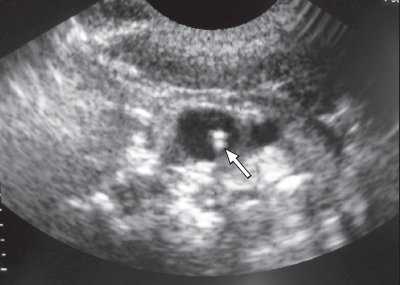

Статическая методика: контрольное УЗИ с визуализацией интересуемых сосудов выполнялось непосредственно перед пункцией центральных вен, разметка на коже наносилась до стерилизации операционного поля (рис.1). УЗИ проводилось в двух взаимно перпендикулярных плоскостях в поперечном и сагиттальном (продольном) сечении между ножками грудино-ключично-сосцевидной мышцы при исследовании внутренней яремной вены (рис. 2, 3) и в паховой складке при исследовании бедренной вены. С помощью предварительного УЗИ определяли глубину расположения вены от поверхности кожи, непосредственно ход венозного ствола, диаметр вены, диаметр артерии, взаимное расположение вены и артерии, степень сокращения (спадения) внутренней яремной вены на вдохе при наличии гиповолемического состояния.

Рис. 1. Предварительная разметка расположения внутренней яремной вены.

Рис. 2. Нормальное расположение и размеры внутренней яремной вены и сонной артерии при исследовании в поперечном сечении.